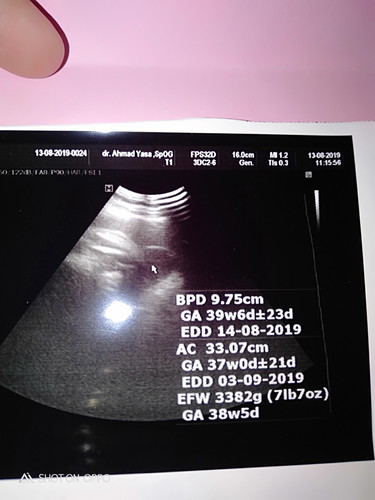

hasil usg

Bu ibu yang saya mau tanya yang benar taksiran lahir hasil USG itu yang mana ya ?

Beda² bun, ambil patokan di hpht aja klau haidnya lancar

bunda 39w apa 38w